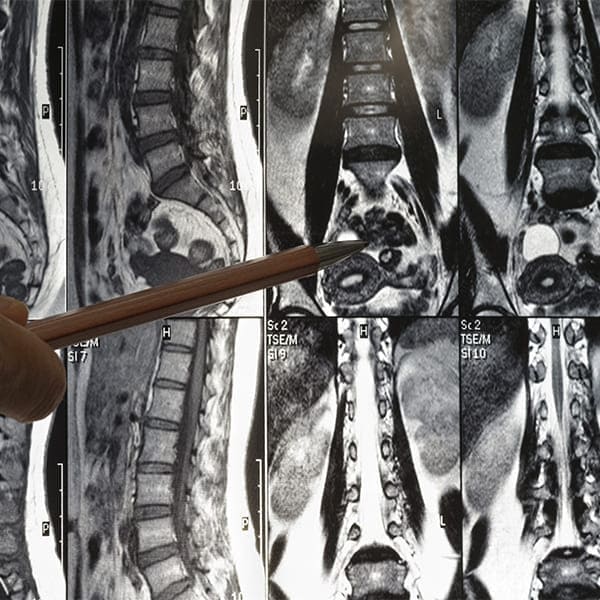

Cuando la estrechez en el conducto lumbar restringe la vida diaria con dolor y limitación de movimiento, la ampliación convencional del conducto lumbar puede ser la solución. Este procedimiento, llevado a cabo por el renombrado Dr. Emmanuel Villanueva, se enfoca en aliviar la presión sobre los nervios raquídeos, restaurando la comodidad y la función.

El Dr. Villanueva emplea esta técnica quirúrgica tradicional para ensanchar cuidadosamente el espacio dentro de la columna lumbar, lo cual es vital para pacientes con estenosis espinal significativa. Cada cirugía se planifica meticulosamente para asegurar que el alivio del dolor y la mejora funcional se alcancen con la precisión que usted merece.